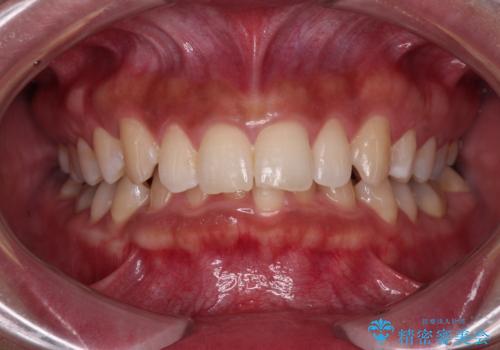

[ セラミック治療 ] 前歯の見た目を改善したい

![[ セラミック治療 ] 前歯の見た目を改善したいの症例 治療前](https://seimitsushinbi.jp/wp/wp-content/uploads/2025/10/IMG_9990-2-500x350.jpg?v=1761816440)

![[ セラミック治療 ] 前歯の見た目を改善したいの症例 治療後](https://seimitsushinbi.jp/wp/wp-content/uploads/2025/10/IMG_9934-500x350.jpg?v=1761816431)